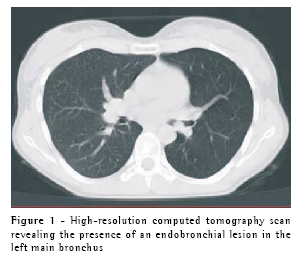

The subsequent high-resolution computer tomography scan revealed the presence of a circumscribed, pedunculated nodule projecting into the lumen of the left main bronchus, without involvement of adjacent mediastinal structures (Figure 1). Bronchoscopy revealed a vegetative lesion that was pedunculated and obstructive, measuring approximately 2 cm in diameter, in the left main bronchus (Figure 2). The patient was later submitted to a posterolateral thoracotomy for isolated resection of the affected bronchial segment, followed by surgical reconstruction of the bronchus. Histopathological examination of the resected segment revealed a lesion predominantly consisting of glandular structures and mucus-producing goblet cells, with no significant cytological atypia. The mitotic index was elevated, which is characteristic of a low-grade endobronchial mucoepidermoid carcinoma (Figure 3). Since being treated, the patient has been asymptomatic and has presented no evidence of recurrence, according to semi-annual monitoring with high-resolution computer tomography and bronchoscopy.

The chest X-ray is extremely important in all suspected cases of recurrent pneumonia since it allows the diagnostician to differentiate between recurrent and persistent pulmonary infiltrates. In many cases, the chest X-ray of a patient who is not currently infected may be normal, and a high-resolution computed tomography scan may help locate the endobronchial lesions.